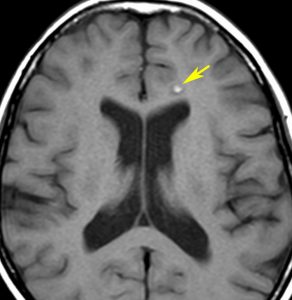

放射線誘発海綿状血管腫,微小静脈閉塞,血液漏出

- 放射線治療を受けた小児患者の4割以上に海綿状血管腫が発生したとの報告があります

- 長期観察をしていると実際に非常に高頻度にみます

- MTX メソトレキセートを使用していると発生頻度が増えます

- 海綿状血管腫は,放射線誘発2次腫瘍というよりも,放射線による脳内小血管損傷による血管障害として捉えた方がよいです

- T2スターというMRI画像で発見できます

- 低信号(黒いシミみたいなもの)として脳内たくさん見られることがあります

- これは血液の中の鉄分が脳に滲み込んだ形跡をみているものです

- だから,海綿状血管腫とは言わないで,blood leak(血液が漏れた痕跡)と読んだ方がいいものです

- 海綿状血管腫というと腫瘍みたいだからです

- 年月の経過とともに数が増加します

- 海綿状血管腫は発生しても何ら症状を呈することはありません

- 治療をせずに放置します

- まれに小さな脳出血を生じますが,経過を見れば血腫は自然に吸収されます

- またサイズが大きな皮質を侵す海綿状血管腫は症候性てんかんを生じることがあります

- とても大きなもの2から3cm以上くらいになると摘出を考えることもあります

- でもほとんど手術などしないでほっておきます

髄芽腫に対する脳脊髄照射36グレイ,8年後のMRI画像です。右前頭葉にごく小さな出血がみられます。その周囲に黒くにじむようなヘモジデリン(鉄)の沈着があります。よく見ると大脳の数カ所に同じような所見がありました。これは脳照射後の微小な静脈の閉塞に起因する血管からの微小な血液漏出 blood cell leakageです。症状を出すこともなく心配ありません。放射線治療後多発性海綿状血管腫と表現されることもあります。